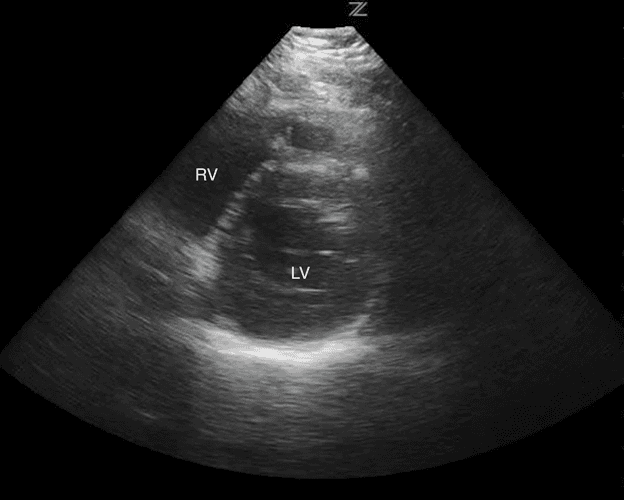

Verwenden Sie die Leber als akustisches Fenster, um das Bild zu verbessern. Der obere Teil des Bildschirms zeigt die Leber des Patienten. Unmittelbar unterlegen zur Leber wird der rechte Ventrikel des Patienten sein und darunter kann man den linken Ventrikel identifizieren. Je nach Blickwinkel kann man in dieser Ansicht auch das rechte und linke Atrium visualisieren (Bild 13).

Subxiphoid markierte Strukturen

Das Abrufen der subxiphoiden Ansicht kann aus zahlreichen Gründen schwierig sein. Dazu gehören der Körperhabitus des Patienten, Darmgas, freie Luft im Thorakoabdominalbereich oder die Unfähigkeit des Patienten, die Untersuchung infolge von Schmerzen zu tolerieren.

Die subxiphoide Ansicht ist die beste Ansicht, um das Vorhandensein oder Fehlen eines Perikardergusses zu beurteilen. 2,17,18 Flüssigkeit aus einem Perikarderguss sammelt sich zunächst in den abhängigsten Teilen des Perikards, nämlich den unteren und hinteren Aspekten, normalerweise um den rechten Vorhof. 19,20 Volumina von nur 15-35cc Flüssigkeit im Perikard können mit Herzultraschall am Krankenbett detektiert werden. 21 Wenn ein Perikarderguss vorhanden ist, sehen Sie auf einer subxiphoiden Ansicht Flüssigkeit zwischen dem Leberlappen und dem rechten Ventrikel am oberen Bildschirmrand (Bild 14).